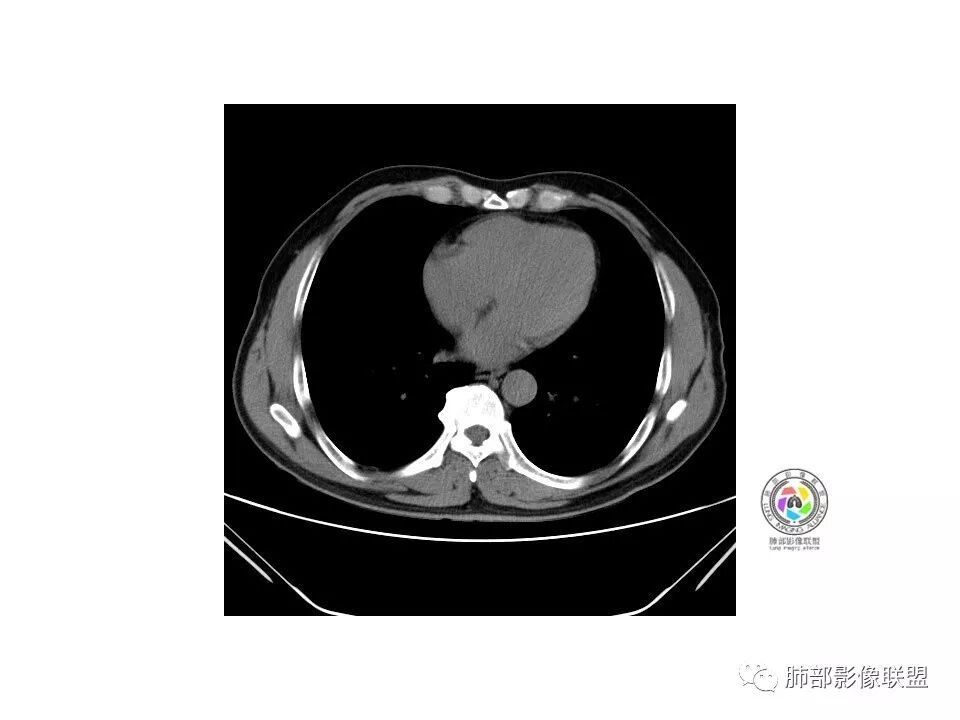

是GGN吗?边界清吗?收缩力?

边界清,收缩力强

血管如何?

血管似有增粗

有增粗,联通、移动,高度怀疑Ca,常规抗炎后复查

病理结果

腺癌